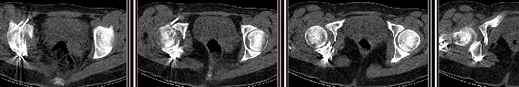

30/11/04 |  30/11/04 |  30/11/04 |  14/12/04 |  14/12/04 |  14/02/05 |  14/02/05 |  21/02/05 | Уважаемые коллеги! Случилось вторичное смещение вертлужной впадины после операции. Посоветуйте, что делать. Пациентка 18 лет. Травма 19.11.04. D.s.: Закрытыый Т-образный высокий перелом правой вертлужной впадины. Закрытый перелом м\мыщелкового возвышения левой б\берцовой кости. 9.12.04 операция - открытая репозиция, остеосинтез переломам вертлужной впадины. 30.12.05 выписаны на амбулаторное лечение с рекомендациями не вставать на правую ногу. 14.02.05 при контрольном осмотре на Р-граммах выявлено вторичное смещение передней колонны. Клинически подвывиха нет, имеется умеренная приводящая контрактура правого тазобедренного сустава, гипотрофия мышц н\конечностей. Госпитализирована в травмотделение. Выполнено КТ. Имеется смещение передней колонны кнутриЮ диастаз 8 мм. Посоветуйте пожалуйста, что предпринять в данной ситуации.

У больной имеется диастаз лонных и седалищных костей, то есть "разорвано" тазовое кольцо. В перспективе возможно образование ложного сустава на уровне основания лонной кости с болевым синдромом, поскольку седалищная кость не срастется.

Сустав-то как раз неплох, поскольку впадина почти вся конгруэнтна, по крайней мере вся нагружаемая часть, и подвывиха бедра нет. Артроз в перспективе тут, конечно, не исключить, но на первом плане проблема целости тазового кольца, т.е. нестабильное несращение, о чем А. Рунков писал. На седалищной дефект, и если и разошедшееся основание лонной не срастется, то болезненные проявления могут быть сразу после начала нагрузки, как ее не отсрочивай.